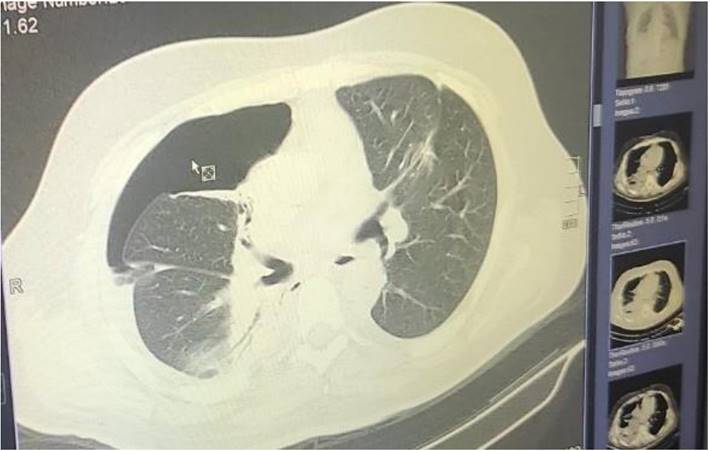

Figure 1

Demonstrates the positron emission tomography findings upon diagnosis red arrow indicates the pulmonary nodule.